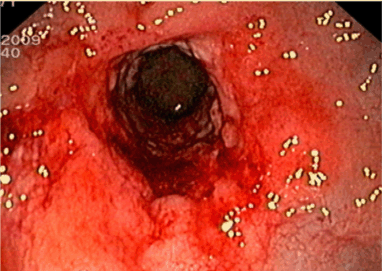

A 71-year-old male patient presented with constipation for one month. No rectal bleeding, pain or tenesmus were associated. Patient did not have a history of contact with or any symptoms of pulmonary tuberculosis. Physical examination was unremarkable, but digital rectal examination revealed hard annular growth about five cm from the anal verge. Colonoscopy showed annular thickening of lower rectum which was covered with a whitish patch. (Figure 1) On suspicision of malignancy, multiple biopsies were taken. Endorectal ultrasonography (B-K Medical HAWK 2102; 2050 anorectal radial probe and a 15 MHz transducer) demonstrated a hypoechoic lesion with pseudopodia. (Figure 2) Computed tomography confirmed a longitudinal circumferential rectal tumor suggestive of malignancy with multiple pelvic lymphadenopathy. (Figure 3) Endoscopic biopsy showed caseous necrosis with inflammatory cells which was suggestive of tuberculosis. (Figure 4) No malignant cells were seen. Chest X-ray showed active pulmonary tuberculosis with positive result for sputum acid fast stain. Anti-HIV ELISA was non-reactive. Serum carcinoembryonic antigen (CEA) was 4 ng/mL. Tissue acid fast stain and tissue culture for tuberculosis were negative. Standard six-month anti-tuberculosis medication was prescribed. The patient responded well to the treatment. His constipation improved. His rectal tumor had receded at the six- month endoscopic follow-up. | ||||||